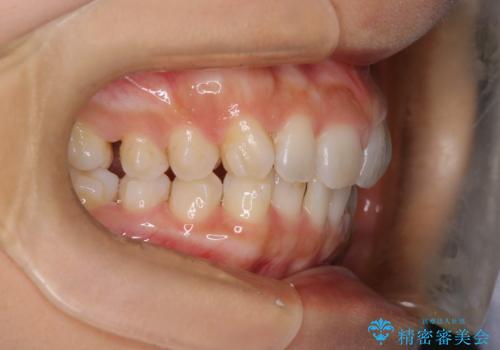

【インビザライン】前歯のねじれを治したい

- 前歯のガタガタを主訴に来院されました。

叢生の量は軽度でしたが臼歯の遠心移動を行い、インビザラインにて治療をしました。

叢生の改善に必要なスペースは遠心移動やIPRで作ることが可能です。今回は遠心移動をメインにスペースを作って叢生の改善を行いました。